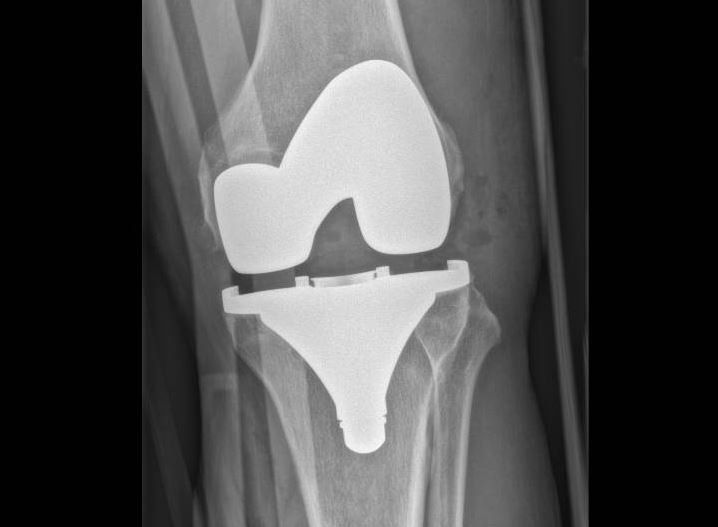

Les Prothèses Totales du Genou (PTG)

Quand l’arthrose atteint tout le genou, c’est la seule option envisageable. Les prothèses de genou vont remplacer les surfaces articulaires du genou.

On les appelle également prothèses tricompartimentales de genou, car elles remplacent les 3 compartiments du genou :

- Compartiment interne/médial ;

- Compartiment externe/latéral ;

- Compartiment fémoro-patellaire (rotulien).

- Les prothèses totales de genou offrent d’excellents résultats à moyen et long terme si les patients sont bien sélectionnés ;

- Les résultats définitifs nécessitent de longs mois de rééducation ;

- Tabagisme, diabète mal équilibré et obésité augmentent considérablement le risque de complications.